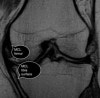

MRI : Normal MCL